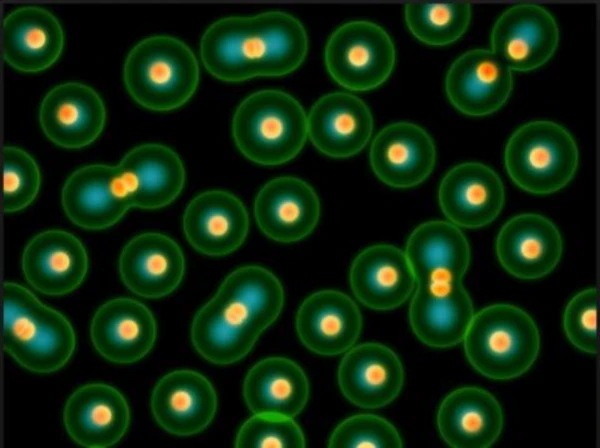

통풍은 주로 체내에 과다 축적된 요산으로 인해 발생합니다. 요산은 우리가 섭취하는 다양한 음식이 소화되어 최종적으로 대사된 후 혈액에 녹아 있다가 소변으로 배출되는 물질입니다. 일반적으로 혈액 내에서 요산은 정상 수준을 유지하며 배설됩니다. 그러나 통풍 환자는 혈액 내 요산이 과다하게 증가합니다. 이러한 과다 축적된 요산은 결정체로 변화하고, 이러한 결정체가 관절 내에 침착하여 염증을 일으킵니다.

통풍 환자는 대개 고요산혈증이라 불리는 혈액 내 요산이 정상치를 넘어선 상태를 가지고 있습니다. 그러나 고요산혈증이 있더라도 모든 고요산혈증 환자가 통풍 환자는 아니며, 무증상으로 고요산혈증인 사람이 더 많습니다. 통풍 관절염은 고요산혈증이 심하고 지속되는 경우에 발병할 가능성이 크며, 발병 확률은 기간이 길수록 높아집니다.